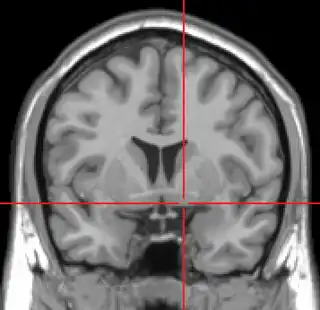

Corte coronal de IRM que muestra la ubicación de la sustancia innominada con la cruz roja. | ||

La sustancia innominada, también sustancia innominada de Meynert —substantia innominata en latín— es una serie de capas del cerebro humano compuestas en parte de materia gris y en parte de materia blanca, que se encuentra debajo de la parte anterior del tálamo y del núcleo lentiforme. Se incluye como parte de la sustancia perforada anterior —llamada así por su apariencia—. Forma parte de las estructuras basales del cerebro anterior e incluye el núcleo basal. Una parte de la sustancia innominada, por debajo del globo pálido, se considera parte de la amígdala extendida.[1]